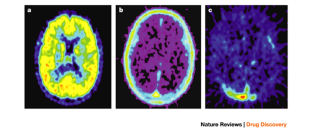

The process of early clinical drug development has changed little over the past 20 years despite an up to 40% failure rate associated with inappropriate drug metabolism and pharmacokinetics of candidate molecules. A new method of obtaining human metabolism data known as microdosing has been developed which will permit smarter candidate selection by taking investigational drugs into humans earlier. Microdosing depends on the availability of two ultrasensitive 'big-physics' techniques: positron emission tomography (PET) can provide pharmacodynamic information, whereas accelerator mass spectrometry (AMS) provides pharmacokinetic information. Microdosing allows safer human studies as well as reducing the use of animals in preclinical toxicology.

Aboagye, E. O., Price, P. M. & Jones, T. M. In vivo pharmacokinetics and pharmacodynamics in drug development using positron-emission tomography. Drug Discov. Today 6, 293–302 (2001).

Hartvig, P., Bergström, M. and Långström, B. Use of positron emission tomography in analysing receptor function in vivo. Toxicol. Lett. 120, 243–251 (2001).

Cherry, S. R. Fundamentals of positron emission tomography and applications in preclinical drug development. J. Clin. Pharmacol. 41, 482–491 (2001).

Gupta, N., Price, P. M. & Aboagye, E. O. PET for in vivo pharmacokinetic and pharmacodynamic measurements. Eur. J. Cancer. 38, 2094–2107 (2002).

We would like to thank Drs Ken Turteltaub and John Vogel at the Center for Acelerator Mass Spectrometry, Lawrence Livermore National Laboratories, USA, for introducing us to the AMS technique. Professors Bengt Langström and Mats Bergström at the PET Cenctre, Uppsala University, Sweden, for their assistance and for supplying Figure 4, and Dr Terry Jones, Manchester, UK, for his assistance on PET. In addition, the financial and scientific contributions of GlaxoSmithKline, Novartis, Pfizer, Janssen Pharmaceuticals and the University of York have proven invaluable to Xceleron Ltd.